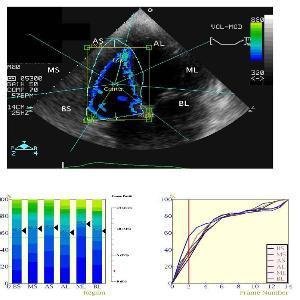

运动负荷超声心动图

心肺运动试验联合运动负荷超声心动图评估心脏储备和运动能力

负荷超声心动图禁忌症